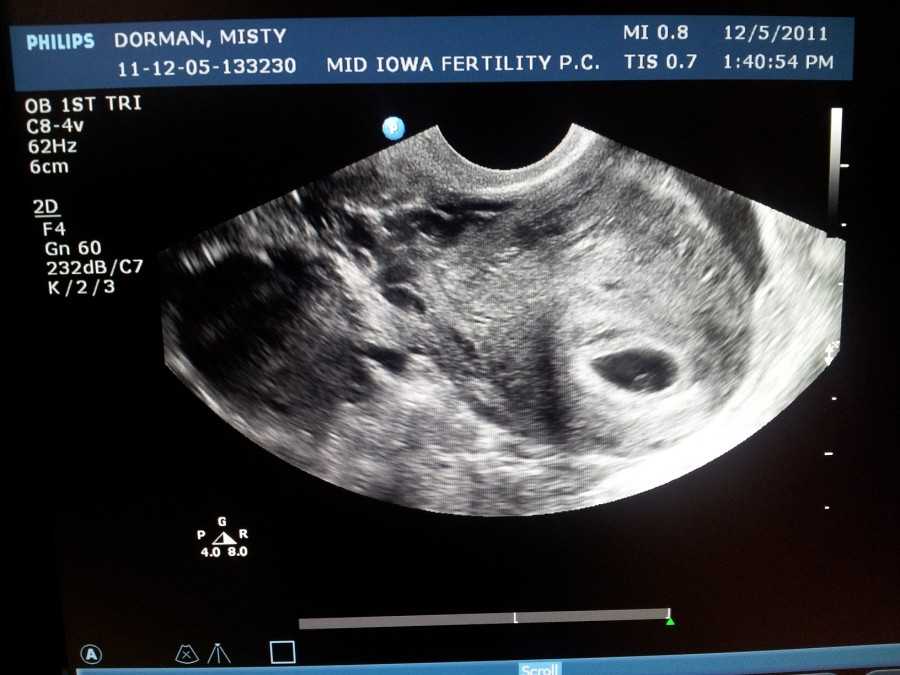

Также показано ультразвуковое исследование плода. Процедура УЗИ позволяет определить срок беременности, толщину плаценты, а также общее состояние яичников и пуповины.

На УЗИ плода на 9 неделе определяется толщина плаценты и общее состояние пуповины. При помощи допплера, будущая мама может отметить частоту сердечных сокращений малыша. Хотя многие внутренние органы уже достаточно развиты, это не всегда можно увидеть на УЗИ на 9 неделе.

Внутренние органы крохи еще могут выступать в виде пупочной грыжи, но нет повода для беспокойства, ведь это совершенно нормальное явление.

На УЗИ на данном сроке обязательным является общая оценка состояния яичников.

УЗИ на сроке 9 недель